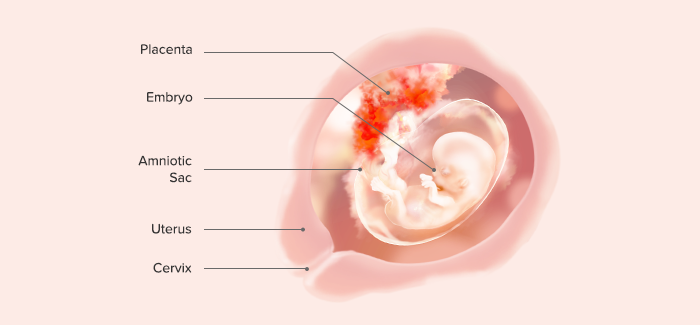

I. End of 4th Gestational Week

At the end of the fourth week of gestation, the human embryo is a group of rapidly growing cells but does not yet resemble a human being.

Length: 0.75–1 cm

Weight: 400 mg

The spinal cord is formed and fused at the midpoint.

Lateral wings that will form the body are folded forward to fuse at the midline.

The head folds forward and becomes prominent, representing about one-third of the entire structure.

The back is bent so that the head almost touches the tip of the tail.

The rudimentary heart appears as a prominent bulge on the anterior surface.

Arms and legs are budlike structures.

Rudimentary eyes, ears, and nose are discernible.